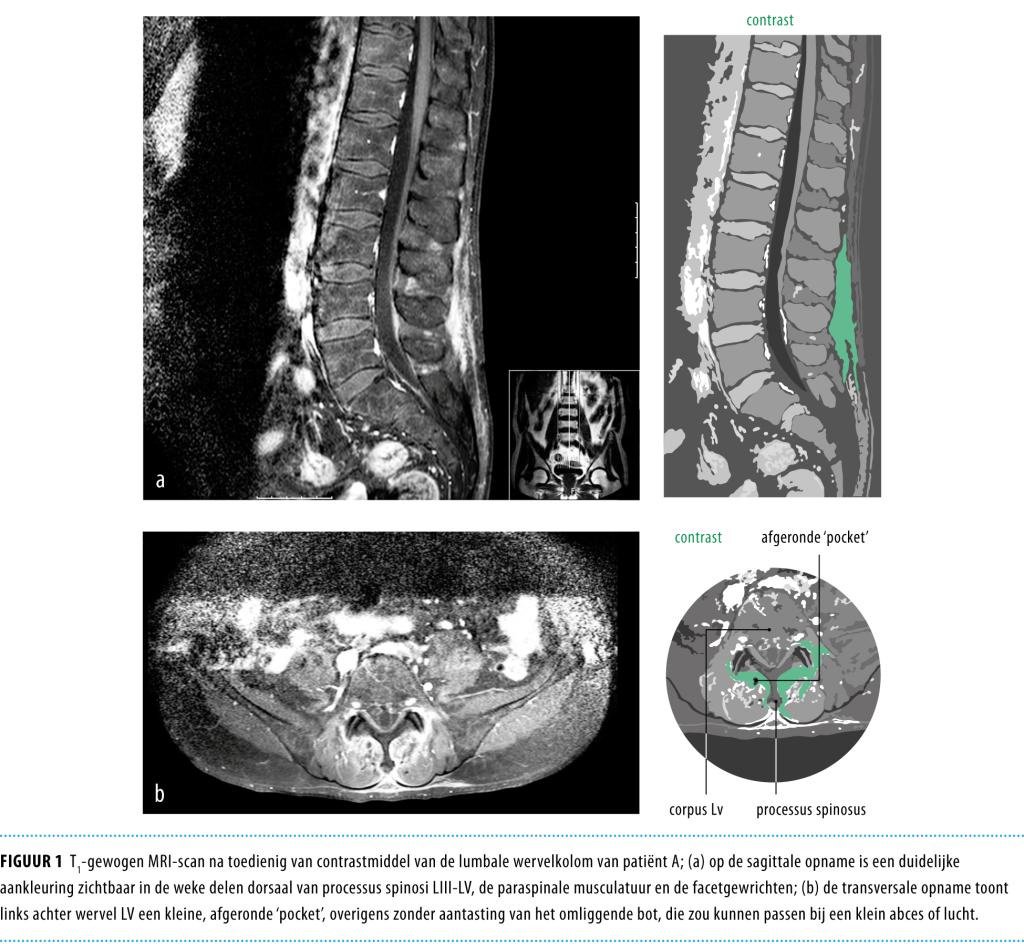

Een 64-jarige man werd opgenomen met toenemende lage rugpijn, uitstralend naar beide bovenbenen. Bij MRI van de wervelkolom werden inflammatoire afwijkingen gevonden bij wervels Liii-Lv, waarop patiënt 6 weken behandeld werd met flucloxacilline. De patiënt knapte echter niet op en de pijnklachten breidden zich uit. Ten slotte werden bij PET-CT afwijkingen gezien in schouders, rug en heupen, waarop de diagnose ‘polymyalgia rheumatica’ waarschijnlijk werd. Onder behandeling met prednison namen de pijnklachten snel af en 3 maanden later waren de inflammatoire afwijkingen bij MRI duidelijk afgenomen. Polymyalgia rheumatica (PMR) wordt vaak herkend aan het typisch klinisch beeld, maar bij atypische presentatie kan beeldvormend onderzoek hulp bieden. Meestal vindt men daarbij afwijkingen in het schouder- of het heupgewricht, maar ook cervicale en lumbale bursitis interspinosa kunnen passen bij PMR.